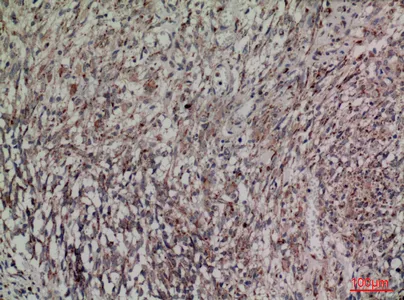

TNF-α Rabbit Polyclonal Antibody

Cat: APRab19095

Size1:50μl Price1:$118

Size2:100μl Price2:$220

Size3:500μl Price3:$980

Size2:100μl Price2:$220

Size3:500μl Price3:$980